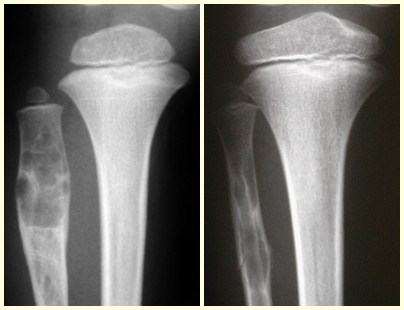

En la evolución puede haber un aumento lento, progresivo o rápidamente expansivo. Afecta a cualquier hueso, con mayor frecuencia a los miembros inferiores, tibia (figs. 57 y 58) y fémur representando el 35% de los casos.

El quiste óseo aneurismático, también llamado quiste hemático multilocular, es una lesión de rarefacción ósea insuflativa llena de líquido serosanguinolento, intercalada con espacios de tamaño variable y separada por septos de tejido conectivo que contienen trabéculas de tejido óseo o osteoide y células gigantes ostoclásticas (figs. 55 y 56).